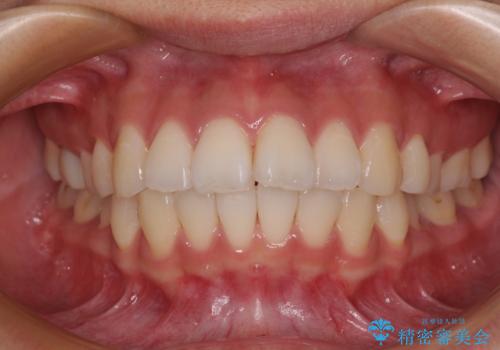

唇を閉じて眠れない ワイヤー装置での抜歯矯正で口元をスッキリと

- 前歯が突出して、眠るときに口が開いてしまうことを気にして来院された患者様です。

横から見た際の口元の飛び出した印象も改善したいとのことで、上下左右の第一小臼歯4本を抜歯し、ワイヤー装置にて抜歯矯正を行うこととしました。

舌の突出癖改善のためのトレーニングをしっかりと実践してくださり、2年強の治療期間でしっかりと仕上げることができました。